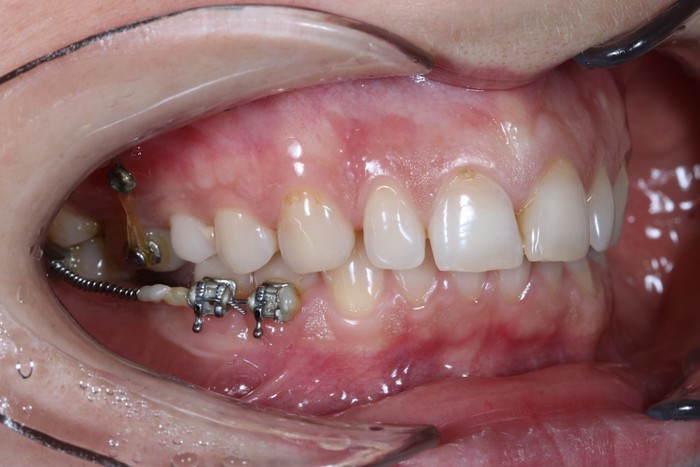

Обратите внимание, необязательно устанавливать полноценную брекет систему для того, чтобы устранить эту проблему. Достаточно приклеить 3 брекета на 4-й, 5-й, и 7-ой зубы, и при помощи специальной пружины толкать проблемный зуб на свое место. На верхней челюсти ситуация несколько иная. Для устранения проблемы устанавливаются два ортодонтических винта. Один со стороны щеки, а второй со стороны неба. К зубам клеятся две кнопки, и дается тяга (специальные резинки). Они-то и «тянут» зуб на место.